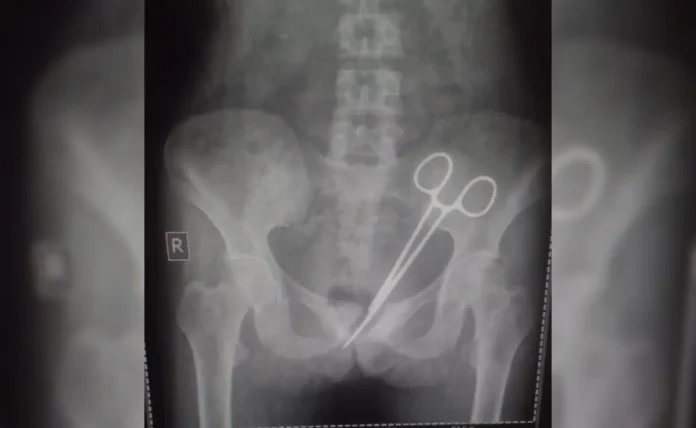

In an unbelievable case of medical negligence, a woman from Sikkim discovered that a pair of surgical scissors had been left in her abdomen for an astonishing 12 years. This horrifying revelation came to light only after she underwent a recent medical examination for persistent pain, which led to an X-ray that revealed the forgotten surgical tool lodged inside her body.

For over a decade, she suffered in silence, with doctors never suspecting the true cause of her pain. It was only during a recent health checkup, after the pain became unbearable, that an X-ray revealed the shocking presence of surgical scissors inside her abdomen. The news came as a devastating blow to Wangmo and her family, who are now demanding answers and accountability.